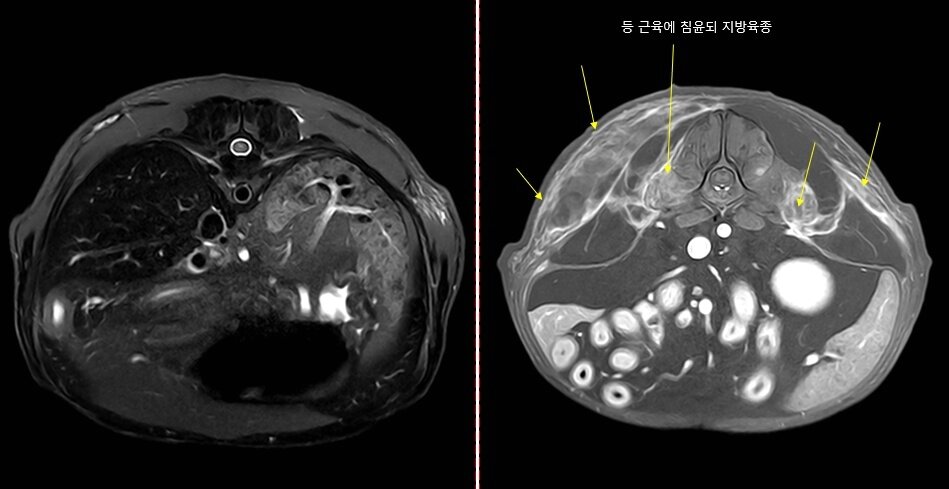

본문 이미지 - 디스크 질환으로 의심됐던 환견의 body MRI 사진.  body MRI 촬영은 국내 동물병원에서는 극히 드문 촬영으로 내장 장기의 움직임을 방지하기 위한 고난도 촬영 기술이 필요하다(동물병원 제공). ⓒ 뉴스1

디스크 질환으로 의심됐던 환견의 body MRI 사진. body MRI 촬영은 국내 동물병원에서는 극히 드문 촬영으로 내장 장기의 움직임을 방지하기 위한 고난도 촬영 기술이 필요하다(동물병원 제공). ⓒ 뉴스1